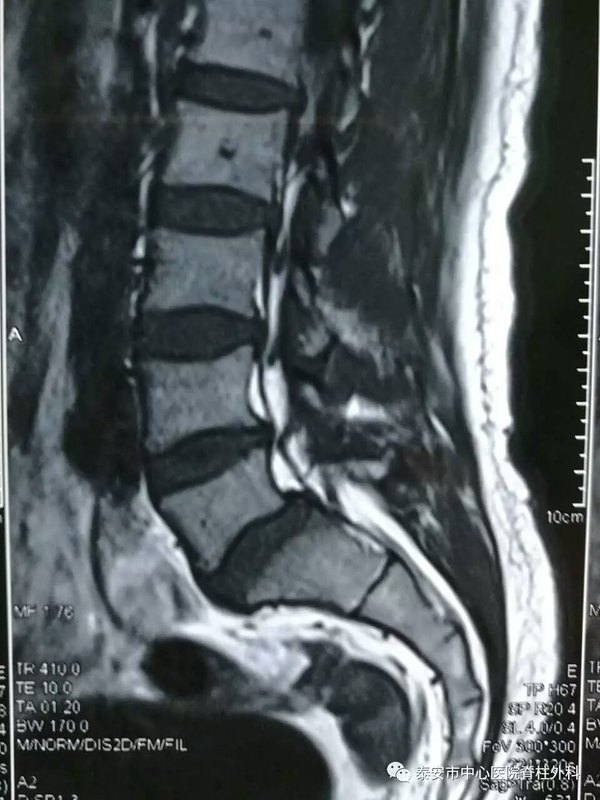

脊柱微創(chuàng)如雨后春筍在世界各地迅速開展,經(jīng)皮椎間孔鏡下腰椎間盤髓核摘除術(shù)(PELD)以其創(chuàng)傷?。ㄇ锌谥恍?毫米),恢復(fù)快(2-3天下地,1周左右出院,1-3月恢復(fù)基本工作),療效滿意(與開放手術(shù)相當(dāng),約94.5%),安全性高(局麻,電視監(jiān)視下取出突出間盤),受到廣大患者歡迎。我院引進(jìn)德國最先進(jìn)的椎間孔鏡系統(tǒng),成功為百余例患者解除腰腿痛。 附幾例典型病例,與大家共享。